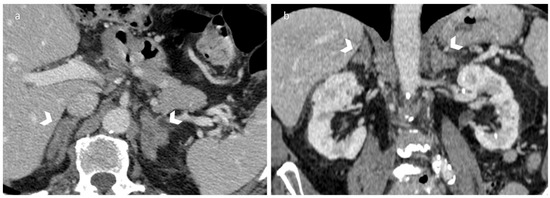

3.2. Metastasis